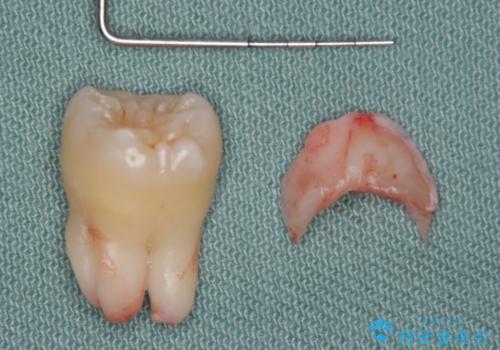

- 親知らず抜歯をご希望で来院されましたが、手前の歯が歯ぐきに覆われていたため抜歯と同時に歯ぐきの除去を行います。

- 親知らず抜歯:保険 ディスタルウェッジ:5,500円費用は治療当時の料金となります

今回は親知らずの抜歯と同時に周りの歯茎の除去を行いました。